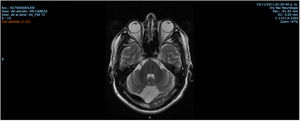

Patient 2 is the index case; he is a 41-year-old male with 5 siblings, 2 of whom have ataxia (Patients 3 and 4 in this report). Symptoms began at age 30; he had recurrent falls due to balance alteration and indistinct lateralized gait, clumsiness to grasp things with his left hand, nasal voice, progressive dysarthria, and spasticity. Mild cognitive impairment and bilateral horizontal nystagmus with slow saccades were found on physical examination (Table 1). MRI revealed decreased cortico-subcortical volume, a retrovermian arachnoid cyst, cerebellar atrophy, and typical hypointense pontine striae (Fig. 4 and Fig. 5).

| Patient 2 (Family 2) | M | 41 | 30 | Ataxia, tremor, dysarthria, spasticity, pes cavus, mild cognitive impairment, nystagmus, complete pyramidal syndrome, decreased sensitivity in distal extremities | Cerebellar and cortical atrophy, hypointense pontine striae, retrovermian arachnoid cyst Fig. 4 and Fig. 5 |